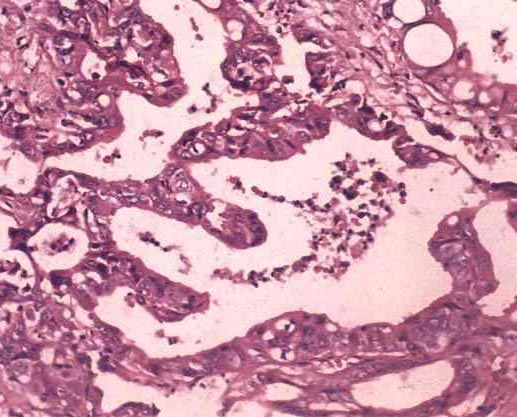

(二)胰胆管合流导常学说 认为由于胚胎期胆总管与主胰管未能正常分离,两者的交接处距乏特(Vater)壶腹部较远,形成胰胆管共同通道过长,并且主胰管与胆总管的江合角度近乎直角相交。因此,胰管胆管吻合的部位不在十二指肠乳头,而在十指肠壁外,局部无括约肌存在,从而失去括鸡功能,致使胰液与胆汁相互返流。当胰液分泌过多而压力增高,使胆管发生扩张。近年开展逆行胰胆管造影证实有胰管胆管合流流高达90~100%,且发现扩张胆管内淀粉酶含量增高这事实。在动物实验中观察到胰液进入胆道后,淀粉酶、胰蛋白酶、弹力蛋白酶的活性增强,这可能是胆管损伤的主要原因。

(三)病毒感染学说 认为胆道闭锁、新生儿肝炎和胆管扩张症是一病因,是肝胆系炎症感染的结果。在病毒感染之后,肝脏发生巨细胞变性,胆管上皮损坏,导致管腔闭塞(胆道闭锁)或管壁薄弱(胆管扩张)。但目前支持此说者已见减少。